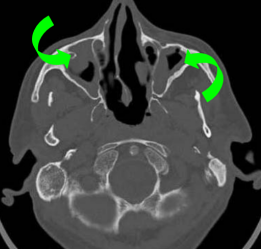

- Polypose Nasale

- Infections ORL (otites, sinusites)